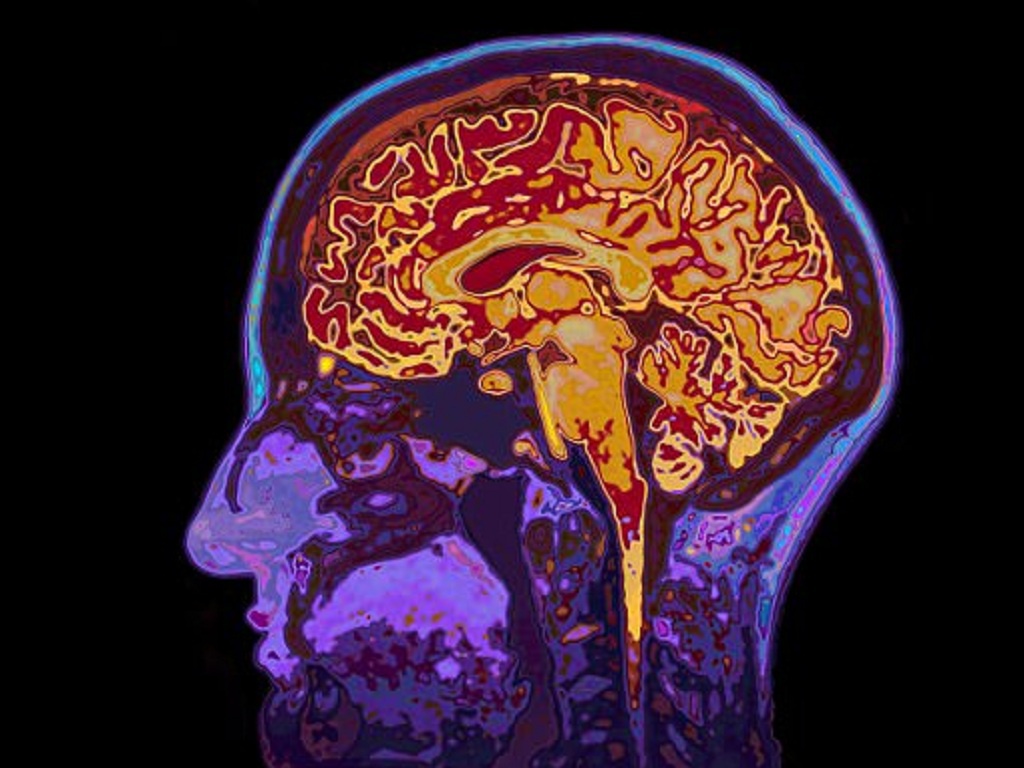

Sau khi thực hiện nhiều kiểm tra, ông Đường bị chẩn đoán nhiễm trùng nội sọ, đa áp xe não, mủ tích tụ nhiều nơi trong não. Đây được xem là nhiễm trùng nặng và nguy kịch đến tính mạng.

Attached Thumbnails

Click image for larger version

Name:	nao-shutterstock_kkqt.jpg